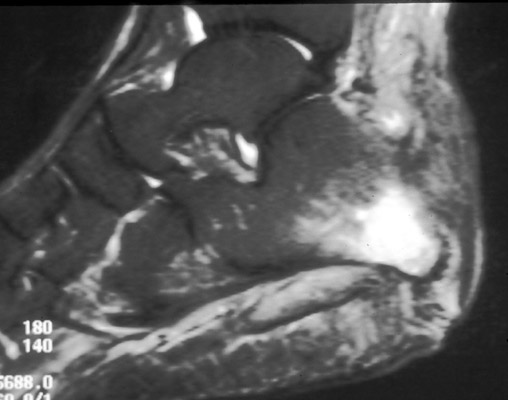

Gout

images/LARGE/72goutMRcor.JPG

images/LARGE/71goutMRsag.JPG

images/LARGE/73goutMRaxt2.JPG

images/LARGE/74goutMRaxpd.JPG